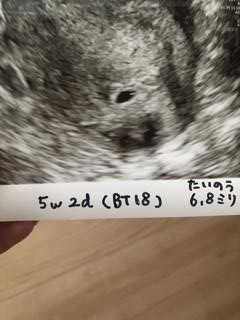

2人目の妊娠。

1人目に続き今回も体外受精で移植4回目、現在(BT18)でやっとここまでこれました!

胎嚢6.8ミリで小さめかなーと。

繋留流産3度経験済みだから、まだ心底喜べないのが悔しいけど、信じて成長を待ってみます!!